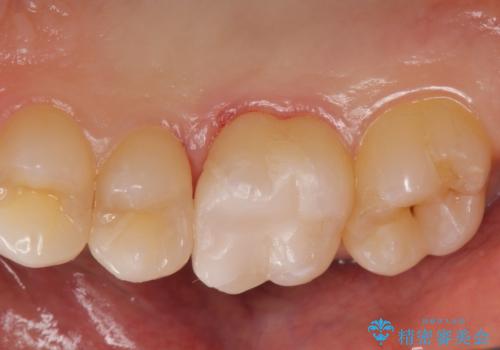

白くて適合の良い詰め物が入りました。

e-maxインレーは保険のインレーに比べて虫歯の再発のリスクが低くなります。